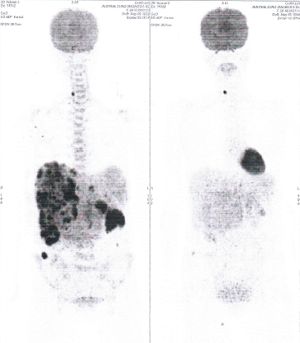

CASE NO: 3 (PROSTATE CANCER)

A middle-aged man with castration resistant prostate cancer, having failed all currently available cancer treatment, was very weak, and getting worse every day. The PET/CT scan showed he had massive bone metastases. After a few treatment, all the bone metastases went into remission. About 6 months later, he is still in remission.